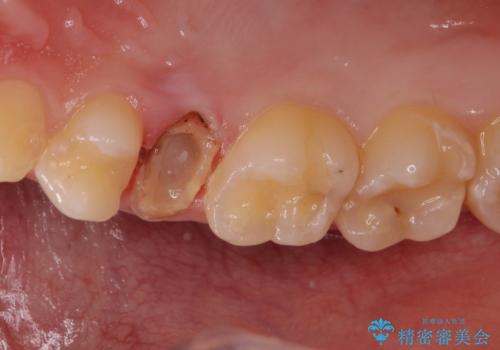

- 「左右どちらとも、どこかが痛む」とご来院された患者様です。

他院で虫歯治療を複数行っており、原因となりうる歯がいくつかありました。まずレントゲン上最もあやしい右上から治療開始しました。右上の歯は1本割れていたため、部分矯正で引っ張り出しました。

他院で虫歯治療を複数行っており、原因となりうる歯がいくつかありました。まずレントゲン上最もあやしい右上から治療開始しました。

右上の被せものを除去したところ、中で歯が割れていたため、部分矯正で引っ張り出すことになりました。